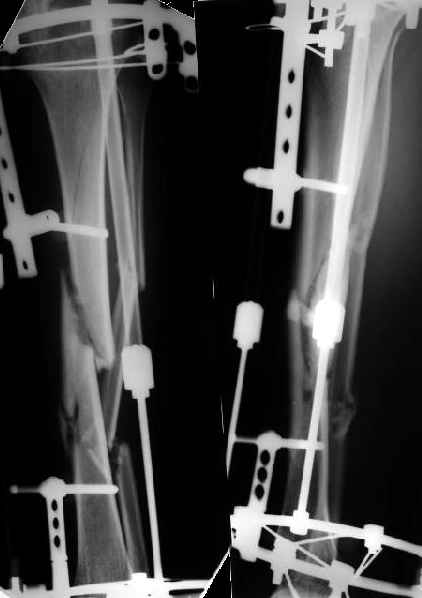

На голени - чрескожная остеотомия малоберцовой кости, закрытая остеоклазия большеберцовой, дистракционный остеосинтез аппаратом.

В плане - востановление длины и оси голени, разработка движеий в колене. Не уверен, что удастся синтезировать голень стержнем при таком маленьком сгибании в коленном суставе.

S> Вальгусную деформацию голени уменшили , но все же есть.

Это же не окончательное положение. Сегодня начали тянуть темпом 2 мм/сут.

S> На бедре в области нижнего перелома остается умеренная варусная

S> деформация.

Мне кажется - скорее, вальгусная... На следующей неделе сделаем еще снимки с захватом коленного сустава, уточним.

Основная проблема - разгибательная контрактура коленного сустава.

Сейчас больному поставлена задача сгибать колено "до первой крови из ушей" - см. фото.

План сейчас - восстановить длину и ось голени. Если колено градусов еще хоть на 20 согнется - заштифтуем, если нет - перемонтируем аппарат для окончательной фиксации. Потом отправим ближе к дому.